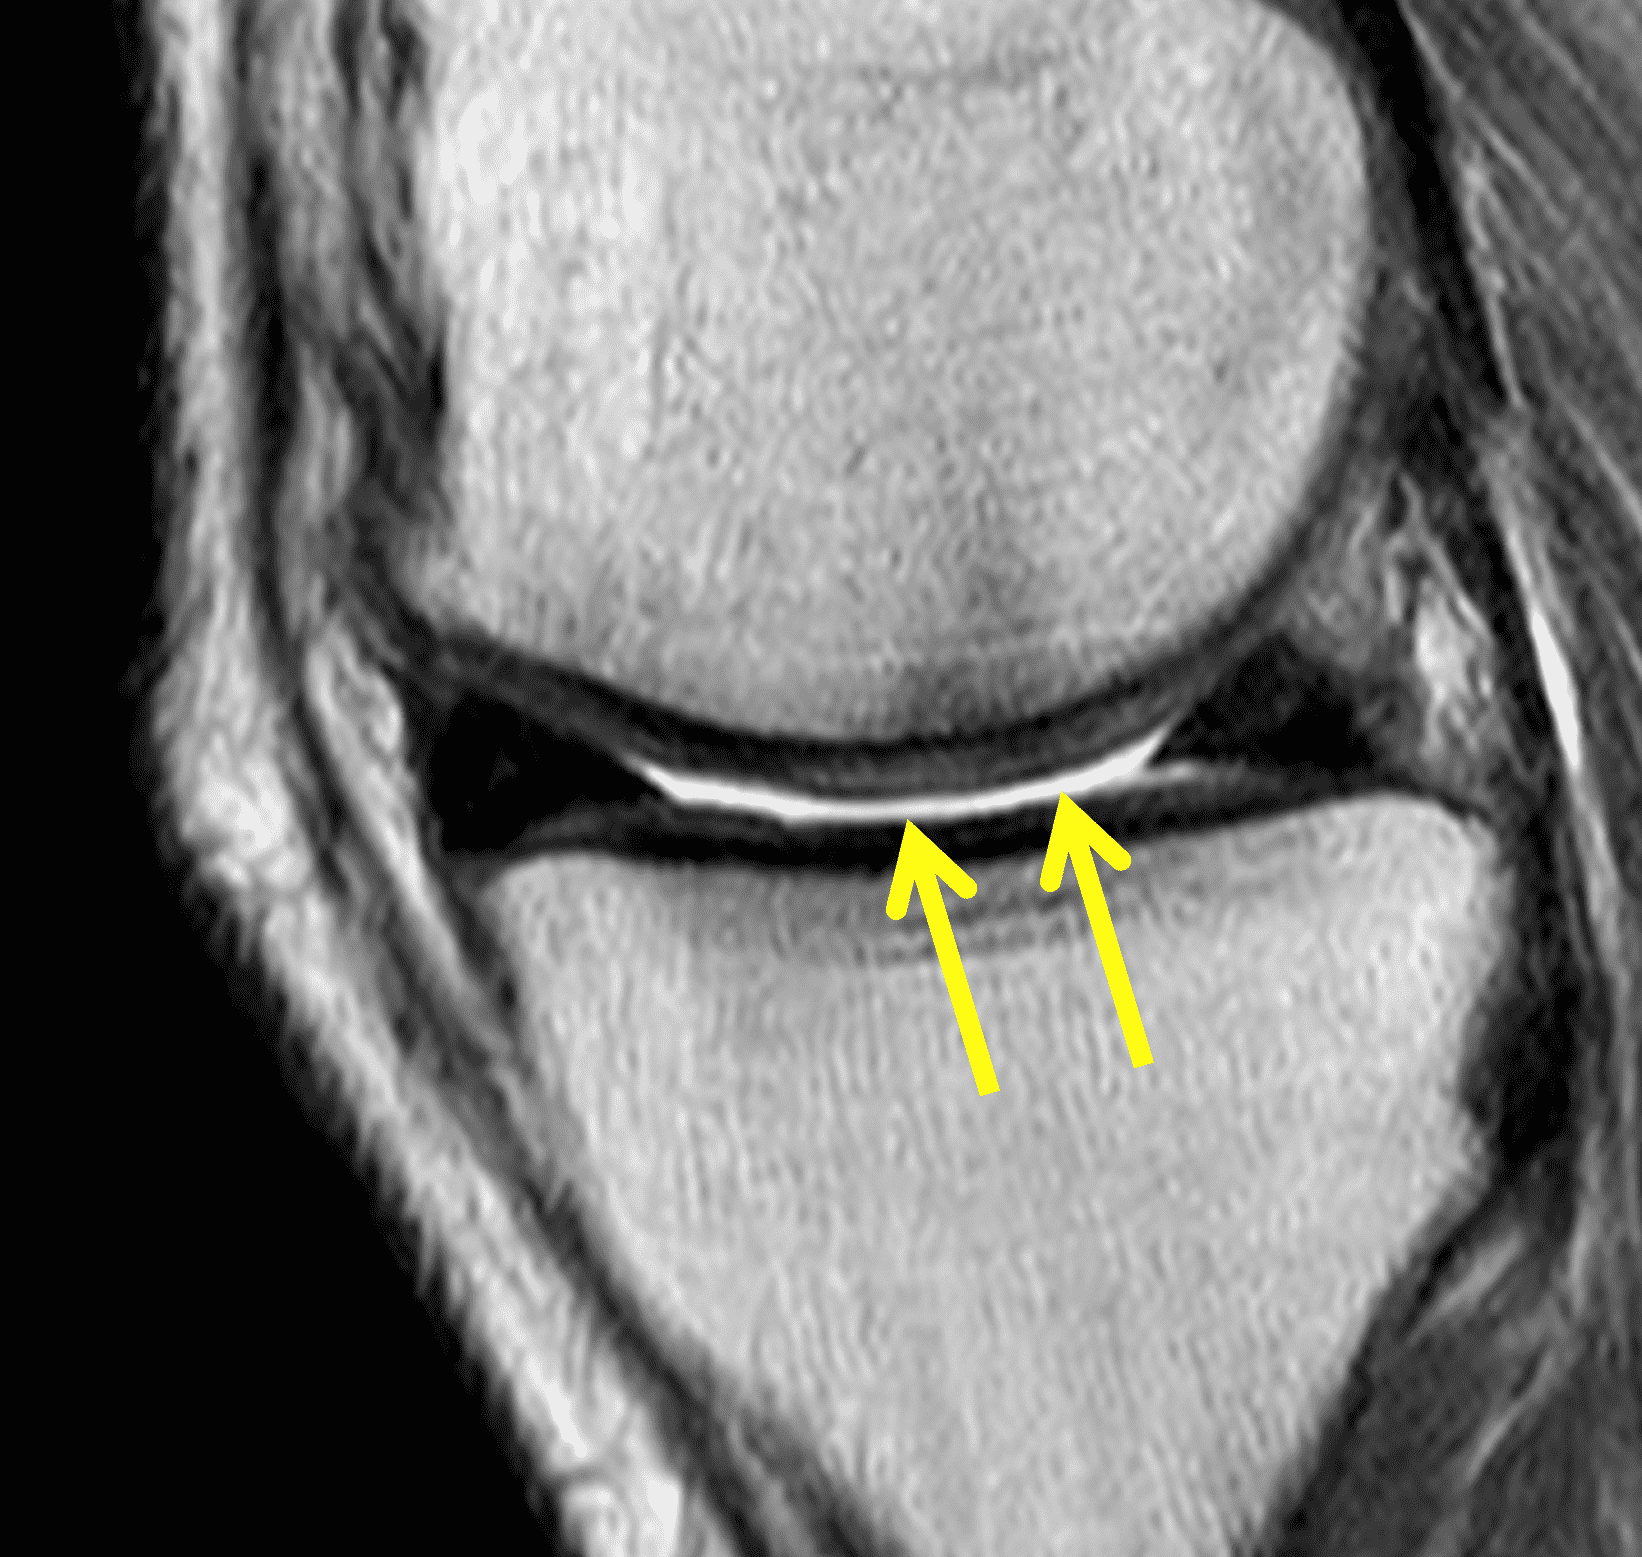

A 32-year-old man suffered a traumatic chondral injury to the medial femoral condyle that was treated with an osteochondral allograft 20 months previously. Representative images from a current knee MRI include (1A) coronal fat-suppressed fluid-sensitive and sagittal (1B) T1-weighted, (1C) proton density-weighted, and (1D) T2-weighted sequences. Are the post-operative MRI findings normal and expected, or abnormal and pathologic? Based on these images, would you characterize the procedure as a success or failure?

Figure 2: (2A) On the coronal image, the margins of the osteochondral graft are faintly visible (arrowheads). Both the graft and underlying bone show mild marrow edema, an expected finding. (2B) The T1-weighted image shows continuity of the marrow in the graft (asterisks) with the underlying bone, indicating osseous integration. A bioabsorbable pin (arrow) used for graft fixation is partly visible. (2C) The proton density-weighted image shows a low signal intensity seam (black arrow) between the native cartilage and transplant, as well as a defect in the subchondral bone plate of the graft (red arrow) where the pin was drilled, both normal findings. (2D) The T2-weighted image shows a smooth, congruent articular surface (arrows), restoring the normal anatomy, and a tiny subchondral cyst. No findings are present to suggest graft failure. The patient’s current symptoms were attributed to pathology elsewhere in the joint (not shown).

Successful osteochondral allograft procedure.

The postoperative imaging appearance of osteochondral allografts is similar to autografts (Figure 2).33 The subchondral bone plate of the donor and recipient sites do not have to match, but the articular surface should be congruent. Grafts that fail to incorporate by one year have a poor prognosis. Persistent marrow edema (beyond 12 months), a thick graft interface containing cysts or fluid, and subsidence of the graft are associated with poor osseous healing and worse outcomes. Extensive host marrow edema and severe synovitis may be a clue to immunologic rejection of the graft (Figure 18).21, 34